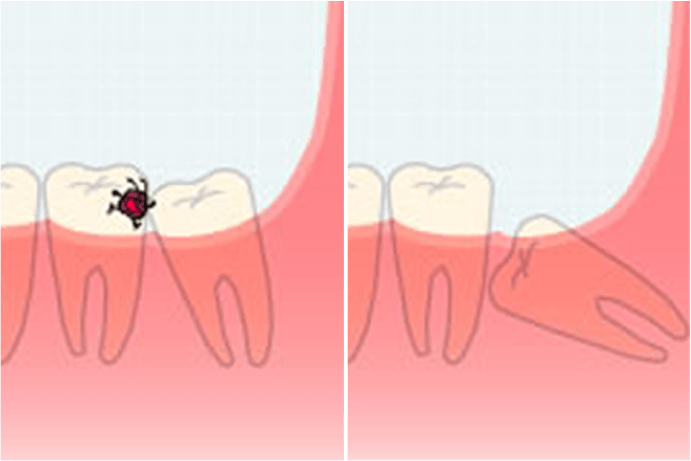

斜めや真横に生えている親知らずの影響で、手前の歯が圧迫され、歯根吸収を引き起こすことがあります。歯根が吸収された歯は、抜歯せざるを得なくなることも少なくありません。

親知らずの虫歯や歯周病が重症化すると、歯の根の先に膿の塊を作ることがあります。その症状が悪化すると、顎骨炎などのさらに深刻な病気へと発展します。

異常な生え方をしている親知らずは、全体の歯並び・かみ合わせを悪くすることがあります。周囲のへの悪影響が大きい場合は、虫歯や歯周病になっていなくても、親知らずを抜歯することがあります。

親知らず特有の病気といえば「智歯周囲炎」です。智歯(ちし)とは親知らずを指す専門用語で、その周囲に炎症が生じるのがこの病気です。いわゆる“歯周炎”とほぼ同じ病気ですが、親知らずではとくに起こりやすいため、特別な名前が付けられています。歯茎の腫れや出血、歯槽骨の破壊などが主な症状となります。